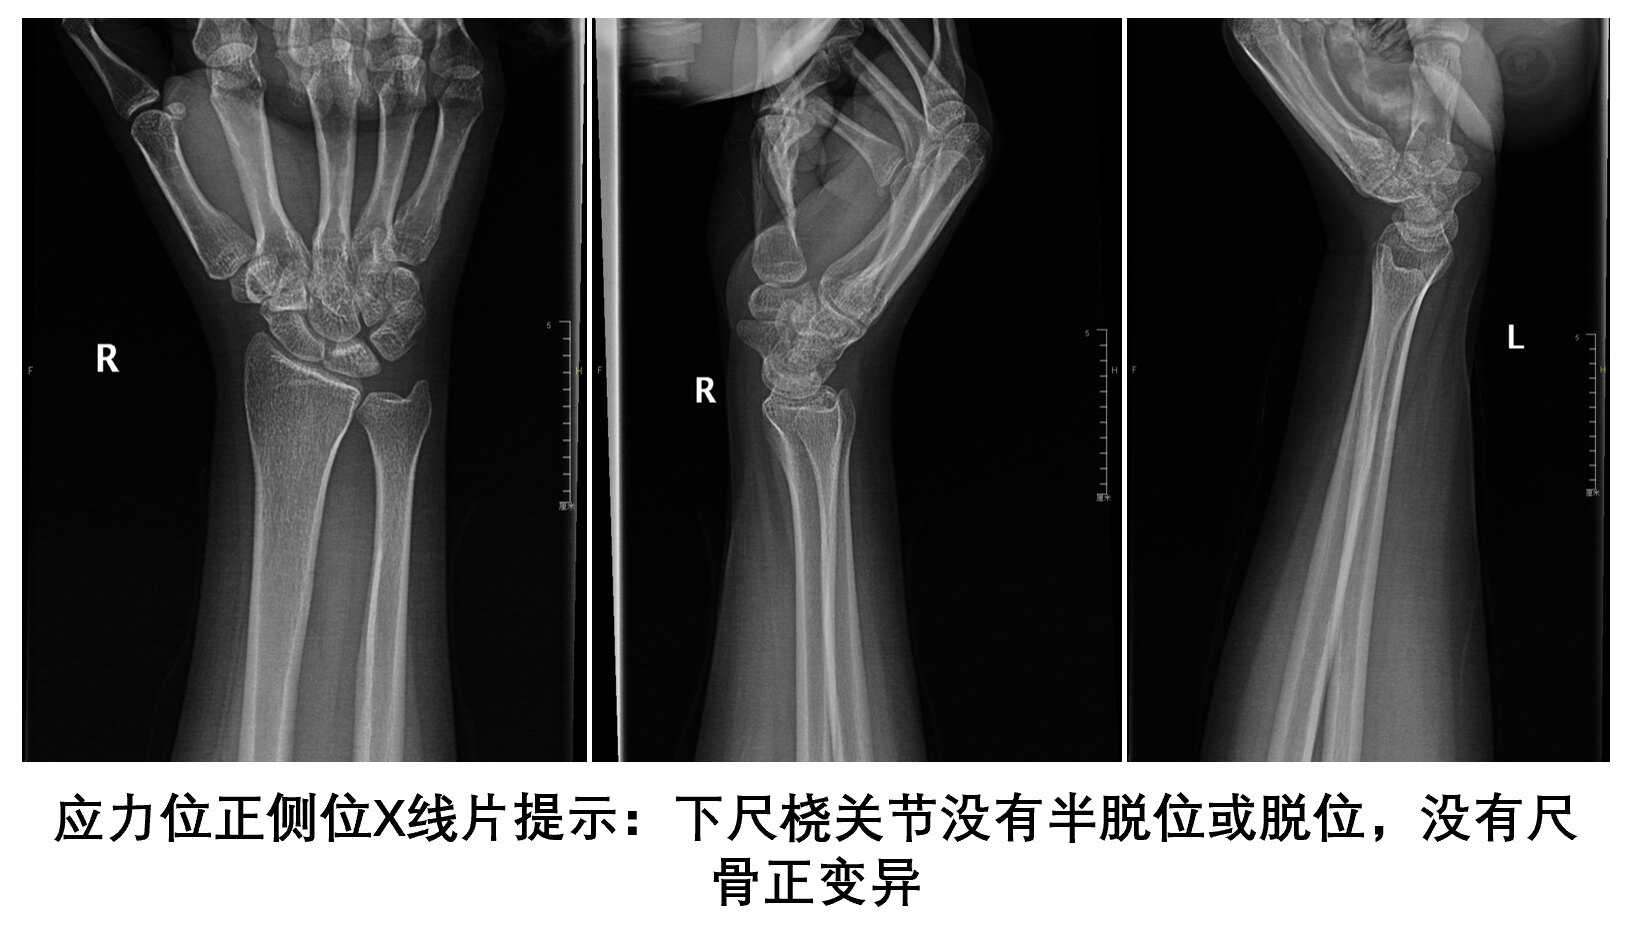

当TFCC损伤明确诊断后,如何确认下尺桡关节不稳定,这里告诉你方法

SEO报道掌长肌腱移植重建背侧下尺桡韧带的解剖结构,疗效满意,下尺桡关节稳定,腕部疼痛缓解。电镜随访,6个月移植肌腱再血管化,纤维结构重建,接近于正常韧带组织。是治疗不合并下尺桡关节炎的陈旧性DRUJ脱位的首选治疗。一、手术方法❶在5、6腕背伸肌鞘管之间,从尺骨茎突水平向近端做长4cm的切口。切开第5伸肌鞘管(小指固有伸),但保留远端部分,牵开小指固有伸肌腱。切开第5间隙底,显露桡尺远侧关节。(注:腕背间隔六个:1拇长展及拇短伸;2桡伸腕长短;3拇长伸;4伸指总及示指固有伸;5小指固有伸;6尺侧腕伸)在DRUJ(桡尺远侧关节)关节囊上切取一L型组织瓣,其中一臂沿桡骨乙状切迹背侧缘,另一臂在平行于桡尺背侧韧带所在位置的近端。向近端及内侧(尺侧方向)牵开关节囊瓣,显露桡尺远侧关节表面和和残留的TFCC近侧面。以探查TFCC的完整性以及修复的可能性。清除尺骨陷窝内的疤痕或失活组织;如果桡尺远侧韧带断裂,TFCC撕裂不可修复,则取掌长肌腱或跖肌腱移植。❷剥离乙状切迹背侧缘处的骨膜以备钻孔作骨隧道。骨隧道定位:月骨窝近端3mm,桡骨乙状切迹桡侧5mm。在透视下用2-4mm空心钻头的导针平行于月骨窝关节面与乙状切迹的表面,从背侧穿至掌侧,3.5mm空心钻头作骨隧道。❸在尺骨远端隐窝和尺骨颈之间之间作一斜行隧道。为了显露隐窝,应该屈曲腕关节,将残留的TFCC牵向远端。导针经隐窝进入,从ECU(尺侧腕伸肌腱)掌侧的尺骨颈穿出。透视证实导针位置合适,用3.5mm空心钻头从近端的尺骨颈向远端的隐窝作骨隧道。❹从腕掌侧横纹向近端在尺神经血管束和指屈肌腱之间作3cm纵向切口,显露桡骨骨隧道掌侧出口。将神经血管束拉向尺侧,屈肌腱拉向桡侧以显露隧道掌侧出口。❺切取掌长肌腱或跖肌腱、伸趾肌腱或FCU(尺侧腕屈肌)FCR(桡侧腕屈肌)的腱束。由于FCU腱束可以从用于重建手术的掌侧入路中切取,并且可以获得很长的移植肌腱,因此作者首选FCU肌腱(尺侧屈腕肌腱)。❻肌腱移植步骤1)切取掌长肌腱或跖肌腱、伸趾肌腱或FCU(尺侧腕屈肌)FCR(桡侧腕屈肌)的腱束,将取线器由背侧向掌侧穿过骨隧道,将移植肌腱一端由掌侧经隧道拉回至背侧。2)在尺骨头和三角纤维软骨复合体残留部位上,用一把直血管自背侧至掌侧穿过(TFC近端)。将直血管钳穿过桡尺远侧关节掌侧关节囊。夹住移植肌腱掌侧端将其拉入尺腕关节,位于三角纤维软骨复合体残留组织近端。注意不要夹持其他肌腱、神经及血管组织。至此移植肌腱的两端均位于背侧手术入路内。3)使用肌腱引导器将肌腱移植物的两端通过尺骨远端的骨通道,自尺骨窝将移植物通过骨通道穿过至尺骨颈近端骨皮质。(肌腱移植物位于TFC近端穿过尺骨凹)4)在尺骨颈(尺侧腕伸肌腱掌侧),在尺侧腕伸肌腱鞘下自桡侧至尺侧、经过尺骨背侧,穿过一把血管钳。用此钳夹住移植物一端,在尺侧腕伸肌腱鞘下,进入背侧切口。(移植肌腱穿出尺骨颈预留的短头)5)在背侧切口,桡尺骨之间,尺骨颈周围,深至尺侧腕屈肌,穿过一把中号直角钳至尺骨颈掌侧中间部(尺侧)来牵引肌腱移植物另一端即预留的长头,自掌侧至背侧尺骨颈周围牵拉肌腱移植物长头至背侧切口。6)肌腱移植物的两端此时应该位于背侧切口和尺骨颈,(穿过尺骨颈的移植肌腱预留长头环绕尺骨颈,自掌侧向背侧穿出)前臂中立位,拉紧肌腱移植物的两侧端,并且用手压紧桡尺远侧关节。在尺骨颈部位移植物两端固定一“半结”。使移植物保持最大紧张度,用3-0韧带线在半结部位缝合肌腱移植物两端。❼3-0线逐层闭合桡尺远侧关节背侧关节囊和伸肌支持带。保留桡尺远侧关节囊上的小指伸肌于皮下组织。逐层闭合掌侧切口。二、康复❶前臂旋后位(旋前型)2枚2mm克针固定尺桡骨,长臂石膏固定6周。防止旋转的腕前臂支具再固定4周。❷10周后开始康复训练,主动活动腕关节及前臂旋转活动,避免被动锻炼!❸4-6个月可以逐渐进行腕关节旋后和旋前锻炼。6个月内避免提重物和施加挤压载重负荷。SEO报道此方法效果较理想,握力可以恢复到健侧的2/3以上,恢复原来工作。手术后前臂旋前、旋后功能恢复接近正常。三、临床病例临床病例五(2021年)xx女xx岁职业医生诊断:右下尺桡关节分离,陈旧右腕TFCC复合体损伤3年,2021.8.7“SEO法肌腱移植重建下尺桡韧带”,3年后随访恢复原工作,疗效评定优。前臂中立位,拉紧肌腱移植物的两侧端,并且用手压紧桡尺远侧关节,复位后用电钻将直径2.0mm的2枚克氏针距尺骨远端1.5cm、2cm处垂直钻入,固定远侧尺桡关节。手术后三年:疗效评定优四、本课题组疗效评定标准:优:前臂旋转活动范围与健侧相似无疼痛,腕部屈伸尺桡活动接近正常,握力接近正常。良好:前臂旋转活动受限<=25%,负重时轻微疼痛,腕部活动范围较手术前明显改善,活动范围达到健侧的75%,握力达到健侧的75%。一般:与健侧比较前臂旋转活动受限<=50%,腕部活动<=50%,活动时轻微疼痛,握力达到健侧50%。差:前臂旋转与腕部活动范围受限>50%,活动时疼痛,握力为健侧的25%以下。小结:1、手术适应证为不合并下尺桡关节炎的陈旧性DRUJ脱位的首选治疗方法。2、桡尺骨远端骨隧道定位准确,1.2mm克针定位,3.5空心钻头钻孔。3、移植肌腱尽可能长,尽可能用取腱器切取,减少切口与疤痕。4、移植肌腱置妥后,进行远侧尺桡关节复位,前臂旋后位2.0克针固定尺桡骨远端。(旋前型)5、拉紧移植肌腱,使其保持最大紧张度,用3-0韧带线在半结部位缝合肌腱移植物两端。6、定期复查,注重康复训练。山西医大二院骨科显微手外科专业组2024年10月30日于太原联系我们:山西医科大学第二医院骨显微手外科病区地点:山大二院五一路院区住院部3号楼7层病区电话:0351-3365107门诊时间地点:周二上午(梁炳生主任医师)山大二院五一路院区骨科门诊1017诊室门诊时间地点:周一上午(梁炳生主任医师)山大二院南院区骨科专家门诊预约挂号:“健康山西网”预约挂号预约加号:“好大夫网”文章部分内容来源于“格林手外科、梅奥手外科卷、坎贝尔手外科卷、津下手外科、手外科全书、韦加宁手外科”等与网络,如果侵权请联系删除。